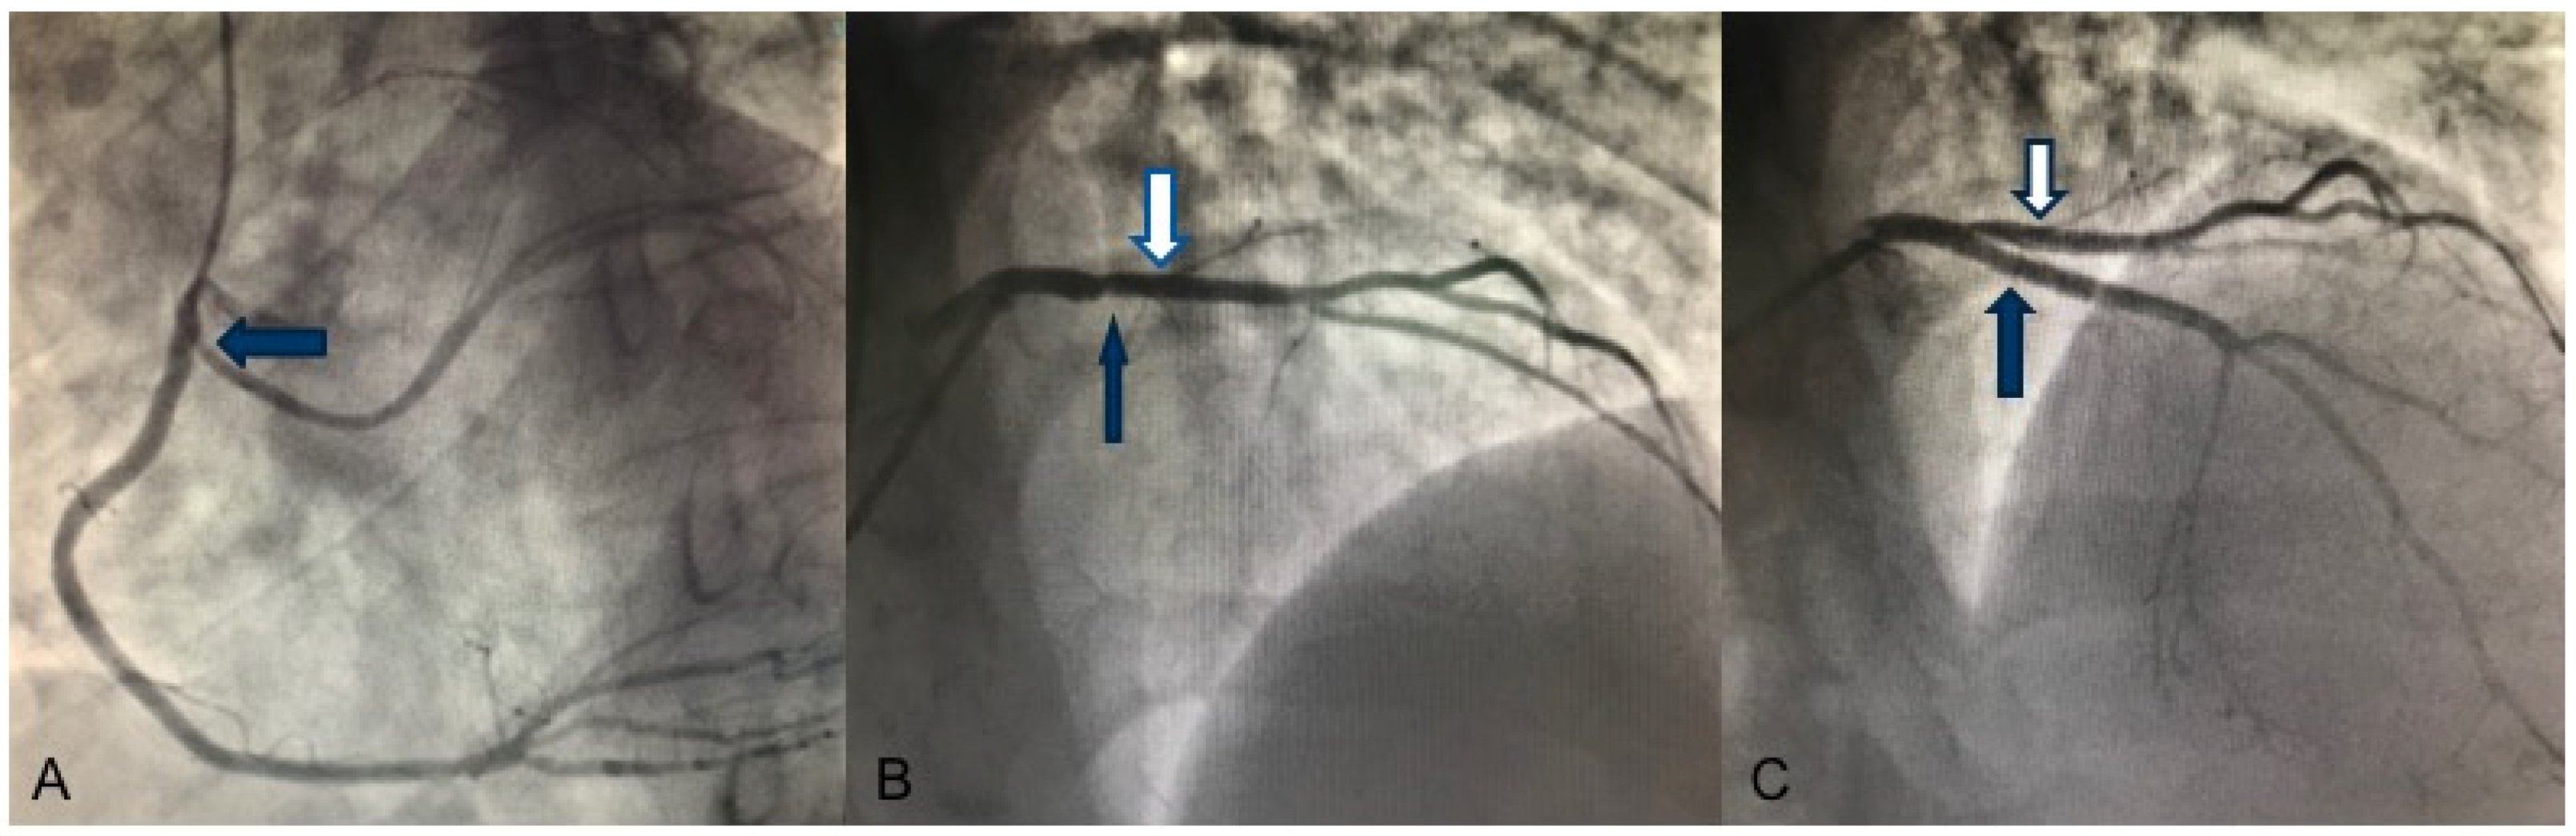

A 33-year-old male, smoker, with family history for sudden cardiac death (father deceased at 54 years old) presented to the emergency room for typical chest pain radiated to the left arm, unrelated to exertion. The physical examination was within normal limits. The laboratory exams showed increased cardiac enzymes levels (Troponin I hs 49,308.7 ng/L, Myoglobin 2494 ng/mL, Creatine kinase-MB 252 ng/mL). The electrocardiogram (EKG) showed ST elevation in the anterior leads and diffuse ventricular repolarization anomalies, suggestive of anterior ST elevation myocardial infarction (STEMI). The patient underwent coronary catheterization, with evidence of anomalous origin of the left circumflex artery (LCx) from the Right Coronary Artery (RCA) (Figure 1A) and critical stenosis on the proximal left anterior descending artery (LAD) (Figure 1B), treated with primary percutaneous coronary intervention (PCI) and implantation of a drug-eluting stent (DES) with a good angiographic result (Figure 1C).

Figure 1.

Coronary angiography. (A) Left oblique angiographic view: anomalous origin of the LCx (blue arrow) from the RCA. (B) Anteroposterior cranial angiographic view: large-caliber diagonal branch (white arrow) and critical stenosis of the proximal LAD artery that appears not viewable (blue arrow) (C) Anteroposterior cranial angiographic view: result after primary PCI and a DES implantation in proximal LAD (blue arrow) with effective restoration of the vessel’s patency and downstream flow. Large-caliber diagonal branch (white arrow).